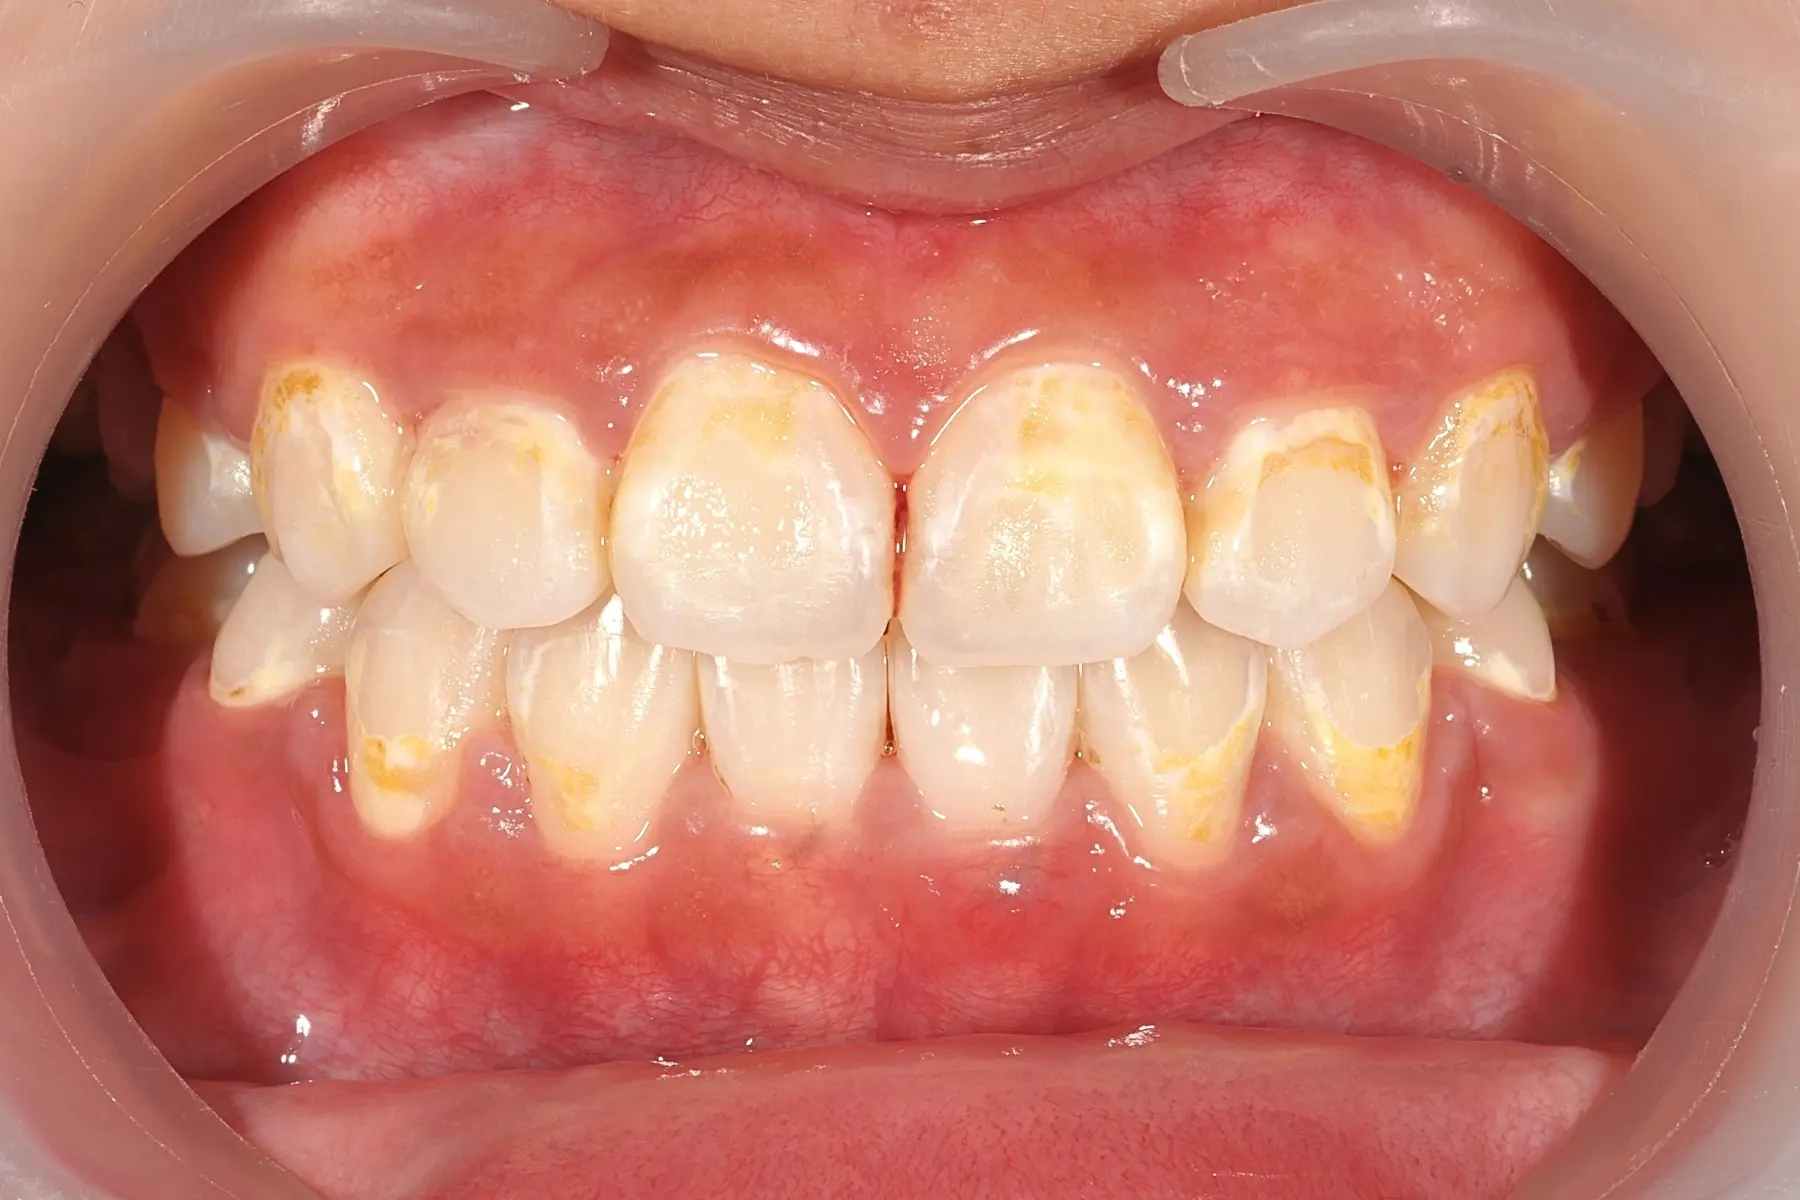

• 術前 42

術後 40

牙周治療

主治醫師

• 鍾國耀

治療時間

三次療程

主訴

右上前牙牙齦反覆腫脹化膿